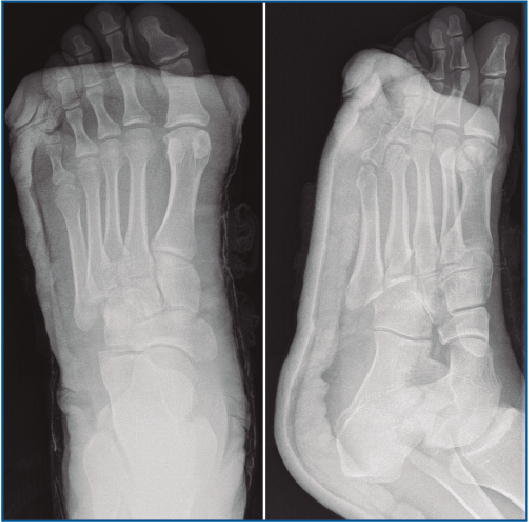

En la exploración destaca una inflamación y dolor en el borde externo del pie que no impide la deambulación. En la revisión de las pruebas complementarias (radiografía simple y TC) se confirman las lesiones previamente diagnosticadas, junto con una luxación del cuboides plantomedial (Figuras 1 y 2).

Figura 1. Radiografía prequirúrgica a la semana de evolución del traumatismo. Obsérvese el desplazamiento medial del cuboides.